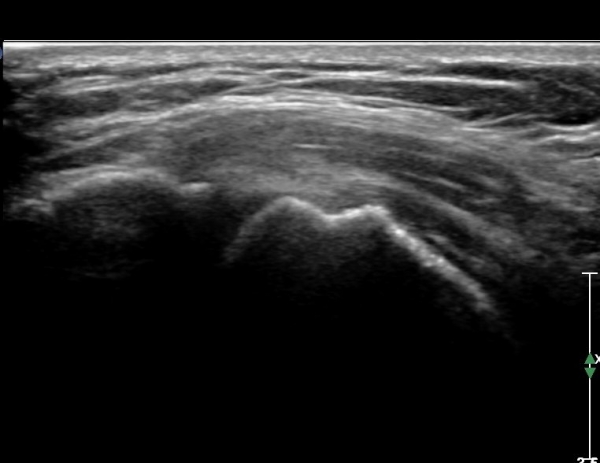

Á߸³À§¿¡¼­ ŽÃËÀÚ¸¦ ¾î±ú ¿ÜÃø¿¡ ´ë°í °ßºÀ°ú ´ë°áÀýÀÌ ¸ðµÎ º¸À̵µ·Ï Á¶ÀýÇÏ¿© ¿ÜÀüÇϸ鼭

Ãæµ¹ ¿©ºÎ¸¦ °üÂûÇÑ´Ù. Á¤Áö »óÅ¿¡¼­ ´ë°áÀýÀÇ °ñ °á¼ÕÀÌ °üÂûµÇ¾î ¸¸¼ºÀûÀÎ Ãæµ¹À»

½Ã»çÇÑ´Ù(»çÁø 8). ¿ÜÀü½Ã »ó¿Í°ñµÎ°¡ »ó¹æÀ¸·Î ¿òÁ÷ÀÌ°í °ßºÀ°ú Ãæµ¹ÇÔÀÌ °üÂûµÈ´Ù(»çÁø 8,

Ã·ºÎµ¿¿µ»ó 1).